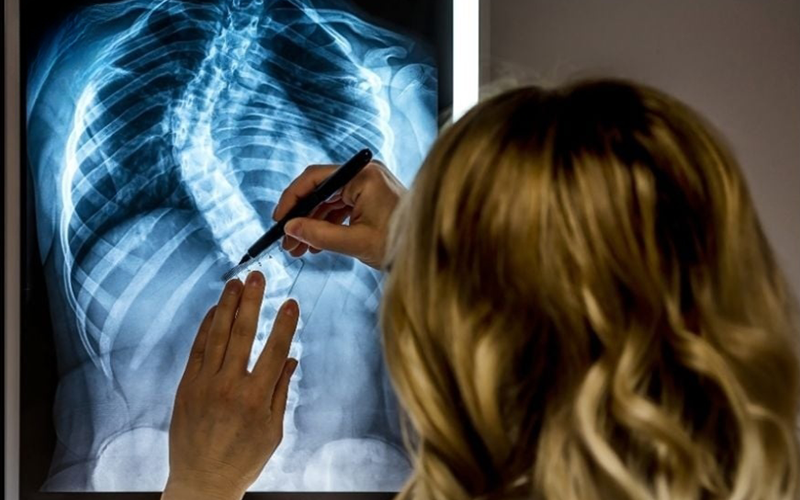

نحوه تشخیص انحراف ستون فقرات

معاینه فیزیکی بررسی علائم این عارضه توسط پزشک مرتبط تصویر برداری مانند ام آر آی، سی تی اسکن و اشعه ایکس